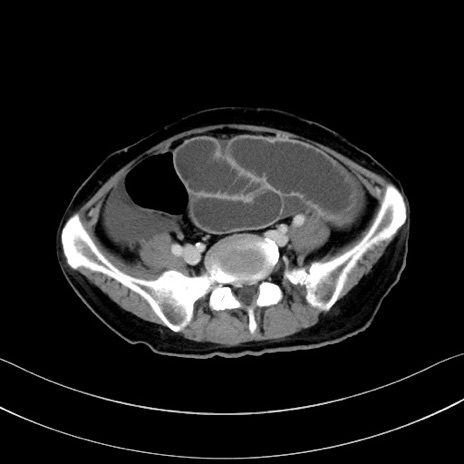

症例28(横断像)

【症例】60歳代男性

【現病歴】胃癌にて胃全摘後。食思不振が悪化し、夜中に嘔吐することがある。

【既往歴】胃癌、胃全摘、脾摘、胆摘後